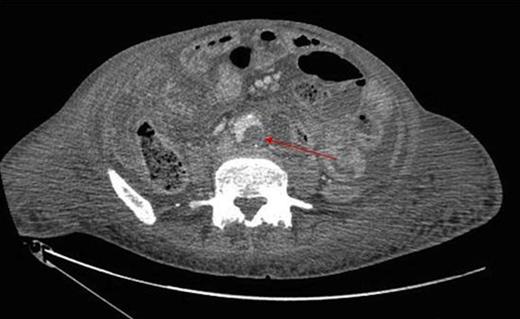

Due to clinical deterioration, a further CT was performed which demonstrated a large communicating collection filling the paracolic gutters and pelvis, with a multiloculated left lobe liver abscess, and a smaller abscess in the right lobe (figure 1). This was percutaneously drained and there was clinical improvement. The patient was discharged home.

During inpatient stay, she became haemodynamically unstable with spiking temperatures and an elevating white cell count. She also complained of bilateral discolouration of her toes and examination revealed increasing oedema with diminished pedal pulses. A contrast CT scan of the abdomen confirmed ongoing collections with evidence of an aortic thrombus extending into the left iliac artery, presumed to be the embolic source for her vascular findings (figure 2 & 3). She underwent a further laparotomy and washout, and was heparinised postoperatively. There was resolution of vascular symptoms and evidence of improvement in peripheral perfusion postoperatively, and the patient was eventually discharged.

Thrombus within the distal aorta shown by a filling defect (red arrow)

Extension into the left iliac artery shown by a filling defect (red arrow)